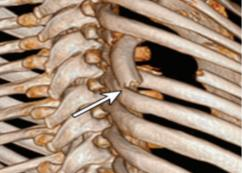

Rib fractures are a common and potentially severe injury that can be challenging and labor-intensive to detect in CT scans. While there have been efforts to address this field, the lack of large-scale annotated datasets and evaluation benchmarks has hindered the development and validation of deep learning algorithms. To address this issue, the RibFrac Challenge was introduced, providing a benchmark dataset of over 5,000 rib fractures from 660 CT scans, with voxel-level instance mask annotations and diagnosis labels for four clinical categories (buckle, nondisplaced, displaced, or segmental). The challenge includes two tracks: a detection (instance segmentation) track evaluated by an FROC-style metric and a classification track evaluated by an F1-style metric. During the MICCAI 2020 challenge period, 243 results were evaluated, and seven teams were invited to participate in the challenge summary. The analysis revealed that several top rib fracture detection solutions achieved performance comparable or even better than human experts. Nevertheless, the current rib fracture classification solutions are hardly clinically applicable, which can be an interesting area in the future. As an active benchmark and research resource, the data and online evaluation of the RibFrac Challenge are available at the challenge website. As an independent contribution, we have also extended our previous internal baseline by incorporating recent advancements in large-scale pretrained networks and point-based rib segmentation techniques. The resulting FracNet+ demonstrates competitive performance in rib fracture detection, which lays a foundation for further research and development in AI-assisted rib fracture detection and diagnosis.